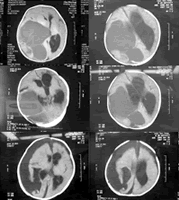

据悉,该婴儿的脑瘤是“促纤维增生性婴儿型神经节细胞胶质瘤”。入院时医学影像检查,患儿头颅内的巨大肿瘤几乎占据整个右大脑半球,前囟被肿瘤撑大,极度扩张。脑组织受压偏向左侧,并产生脑积水。巨大肿瘤和脑积水双重压迫脑组织,致使患儿颅内高压,产生昏迷等症状。

鲍医师依据新生儿前囟未闭的特点,设计了一个全新的治疗方案,即第一步抽取肿瘤囊液,以减轻颅内压,2次穿刺放液120 ml;第二步,待脑疝好转,患儿生命体征稳定,进行肿瘤切除术。患儿出院时,已经能吃、能看、会笑、会抬头,生长发育趋于正常。, 百拇医药